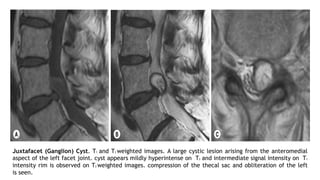

Juxtafacet (Ganglion) Cyst. T1 and T2 weighted images. A large cystic lesion arising from the anteromedial

aspect of the left facet joint. cyst appears mildly hyperintense on T2 and intermediate signal intensity on T1

intensity rim is observed on T2 weighted images. compression of the thecal sac and obliteration of the left

is seen.